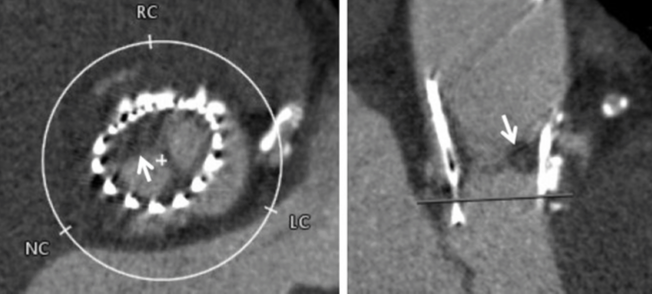

O implante valvar transcateter tem revolucionado o tratamento de pacientes com estenose aórtica severa e que possuem elevado risco para…

Exames de imagem são essenciais no planejamento, execução e acompanhamento de procedimentos cardíacos. Eles possibilitam a obtenção de dados morfológicos…